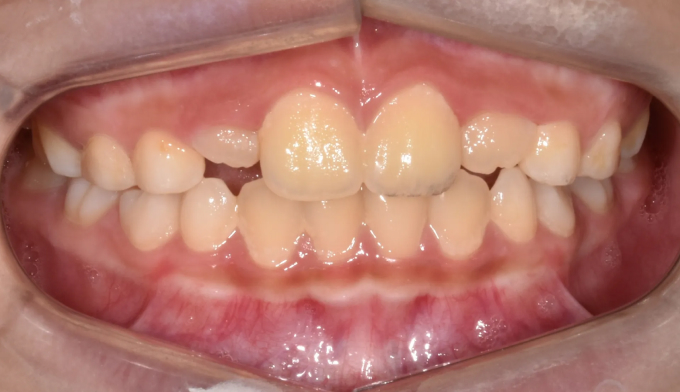

앞니가 거꾸로 물리지만 위턱과 아래턱뼈 검사상 정상 수치를 보이는 경우입니다.

이런 경우 간단한 근기능장치 교정으로 앞니교합을 정상으로 만들어줄 수 있습니다.